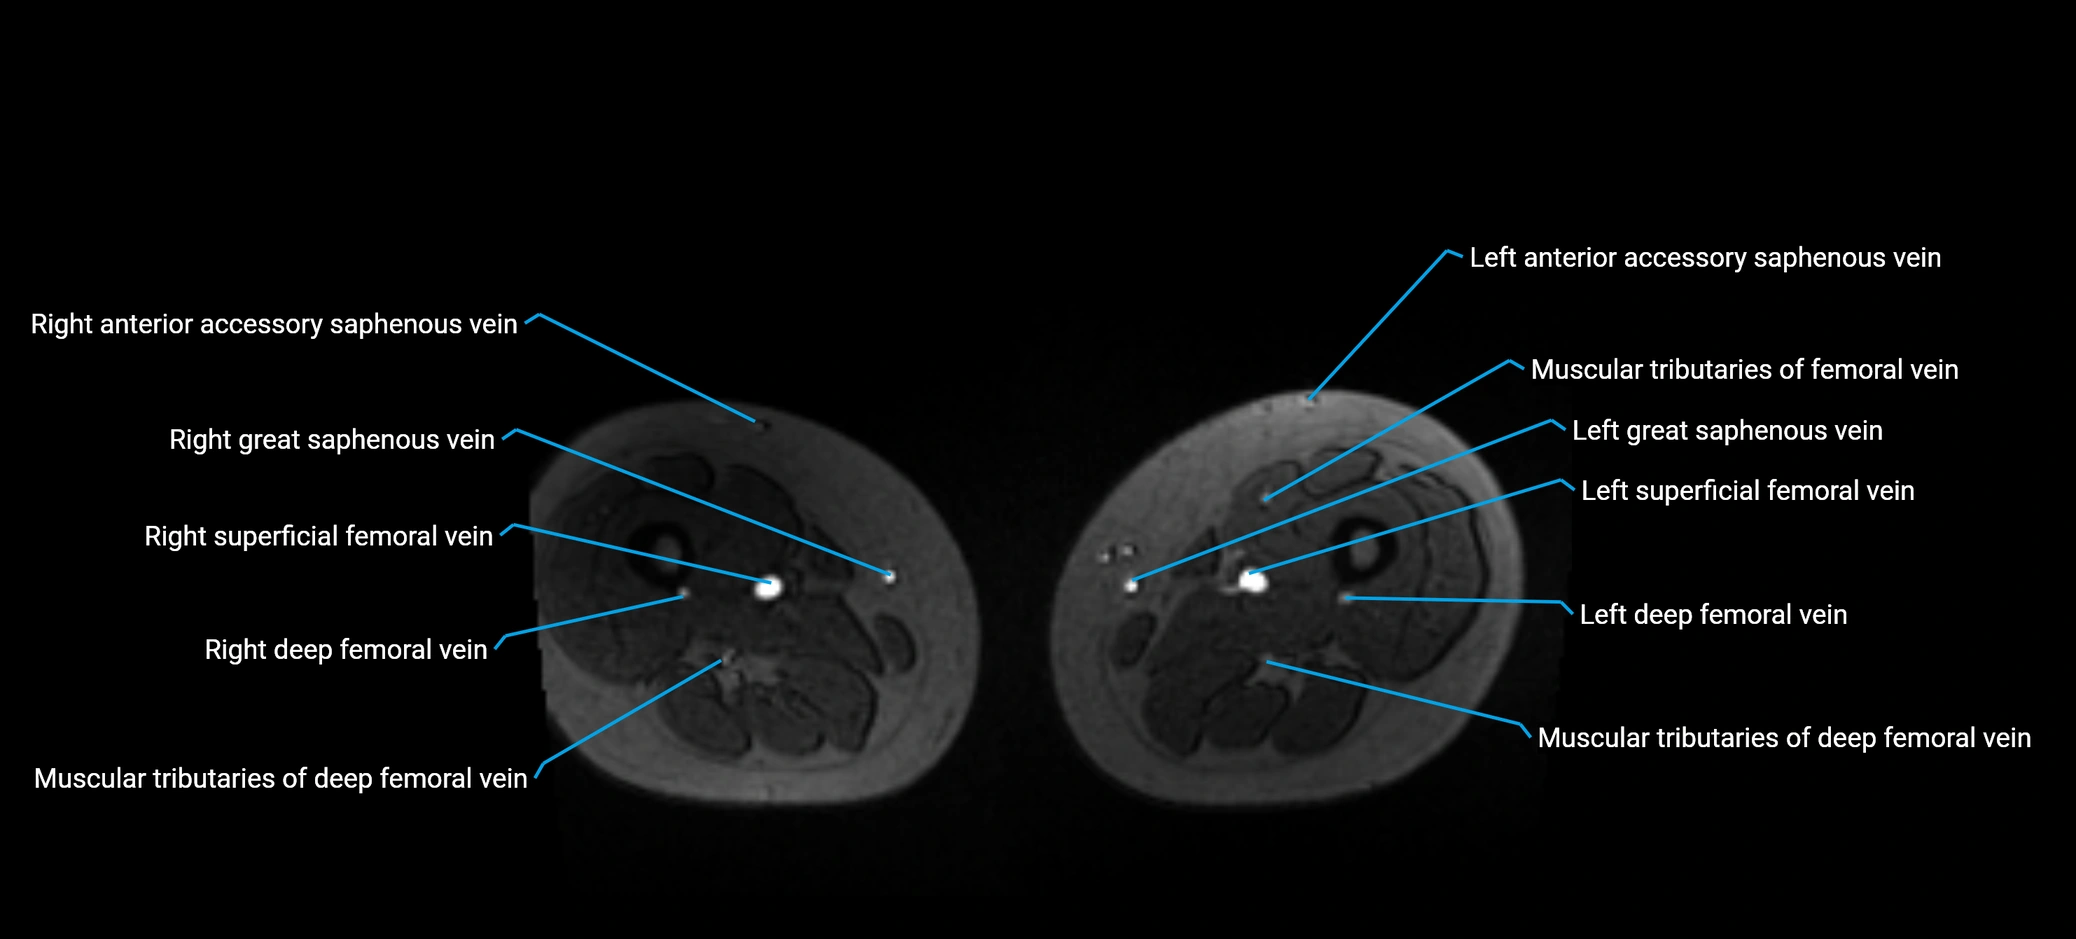

MRI image

image